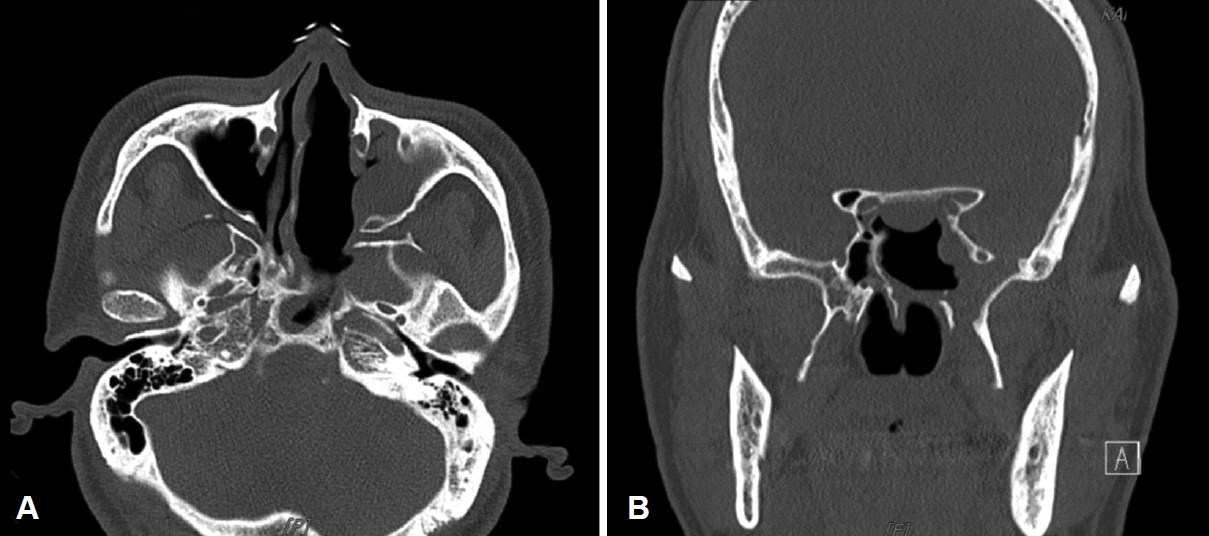

이러한 결과들을 종합하여 전신마취하에 내시경적 비강 내 종물 절제술을 시행하기로 계획하였다. 좌측 중비갑개는 종물의 압박으로 인해 매우 얇아져 있었으며 비중격은 우측으로 심하게 만곡된 상태였다. 네비게이션을 사용하여 종물 주변의 해부학적 구조를 확인하면서 전방에서부터 라디오 주파수 코블레이션(radiofrequency coblation)을 사용하여 종물을 제거하였다. 종물의 크기가 커 한 번에 제거하기 어려웠기 때문에 라디오 주파수 코블레이션을 사용하여 크기를 일부 줄이면서 유착된 부위를 확인하며 절제하였다. 좌측 접형동, 사골동, 상악동에서 종물로 인한 이차적인 부비동염 소견이 관찰되었으며 종물은 좌측 접형동의 하외측벽에 부착되어 하비갑개의 전방부까지 확장되어 있었다. 이를 통해 익돌관 신경에서 기원한 것으로 추정할 수 있었다. 절제 중 종물에서 출혈이 발생한 경우에는 라디오 주파수 코블레이션을 이용해 지혈하였다. 종물 제거와 함께 좌측 사골동 절제술 및 접형동 절제술을 시행하였으며 좌측 접형동 골벽의 미란이나 출혈이 있는지 확인한 후 수술을 마쳤다. 수술 중 추정 출혈량(estimated blood loss)은 30 mL였으며 환자는 수술 후 특별한 합병증 없이 다음날 퇴원하였다. 수술 후 조직병리학적 검사상 종양은 얇은 교원질 섬유가 불규칙적으로 증식하고 물결 모양의 핵을 가진 방추형 세포들로 구성되어 있었다. 또한, S-100 단백질에 대한 특수염색 결과 양성 소견을 보여 신경섬유종으로 최종 진단되었다(Fig. 4). 이후 수술 경과 1년까지 눈물 분비 감소나 비강 건조증 등의 추가적인 이상소견 없이 경과 관찰 중이다(Figs. 5 and 6).

Histologic findings. A: The tumor showed irregular proliferation of thin collagen fibers and spindle-shaped cells with wavy nuclei (hematoxylin and eosin, ×400). B: Positive immunoreactivity for S-100 protein was observed in tumor cells (×400).